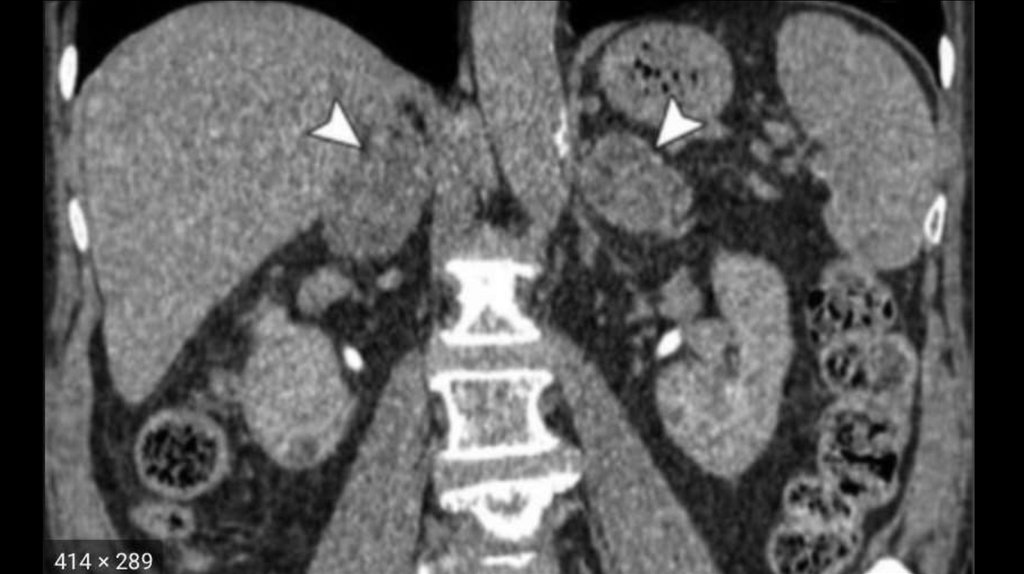

20. МРТ/КТ

• ◊ При МРТ в сочетании с контрастированием гипофиза

(гадолиний) аденома выявляется в 80% случаев.

• ◊ Однако следует иметь в виду, что аденома гипофиза выявляется

у 10% лиц без нарушения функции гипофиза, поэтому

биохимические исследования гормонов имеют решающее

значение.

• ◊ В случае подозрения на АКТГ-независимый синдром Иценко –

Кушинга при МРТ/КТ в надпочечниках можно выявить

характерные морфологические изменения.